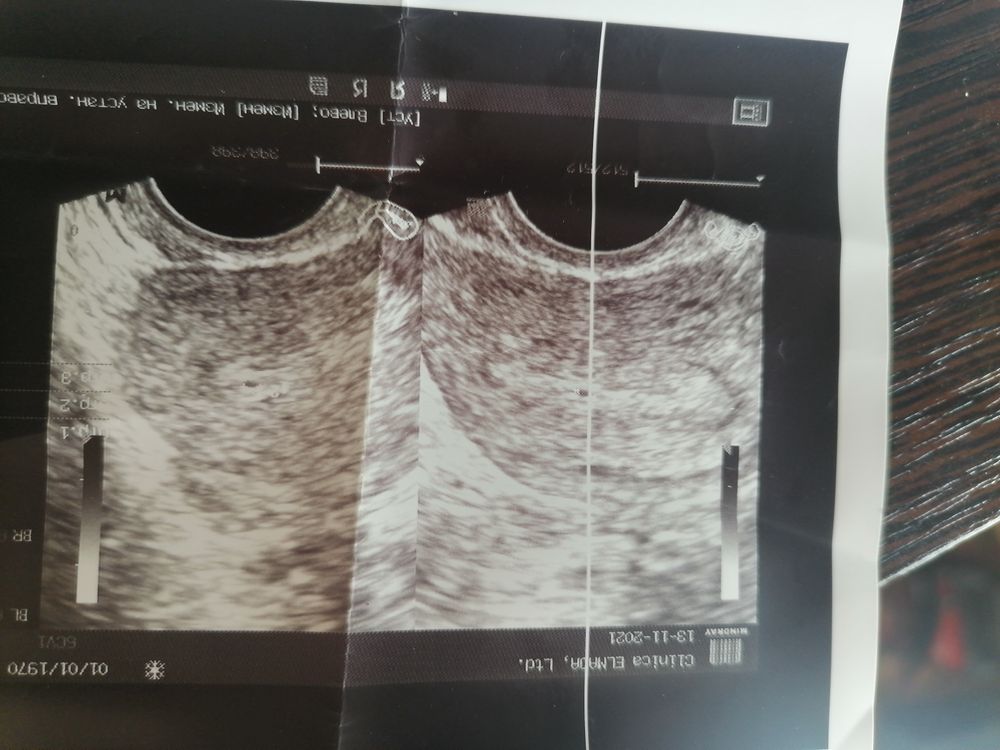

Истории из жизниДевочки здравствуйте. Цикл не регулярный 28-35 дней. Прошлый цикл был 35 дней последние месячные 9.10.2021. 6 ноября закрались подозрения сделала тест а там вторая полосочка бледная. Через пару дней повторила уже поярче и так 10 тестов. Хгч кровь 13.11 был 59.8. 22.11.2021 пошла на узи ничего не увидели ни в матке ни в трубах. У кого так было. На днях пойду ещё кровь сдам. У меня 2 детей и такого никогда не было. Если Б была то всегда тест показывал, если её не было то даже и призраков не было чистый тест

Так же на узи 13 ноября нашли пя 1.8 мм а другой узист сказал ничего нету вот не знаю что думать (((((( так хочется лялю. 1.5 года после зб прошло очень боимся